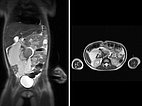

Erster Fall eines 5 Jahre alten Mädchens mit aufgetriebenem Abdomen. Im koronaren und transversalen T2-gewichteten, fettunterdrückten MRT ausgedehnte LM mit großen Zysten, die den Darm verdrängen.

Die fettgesättigte, T2-gewichtete MRT in drei Schichtebenen zeigt die Ursache: Riesige Zysten retroperitoneal einer makrozystischen LM.